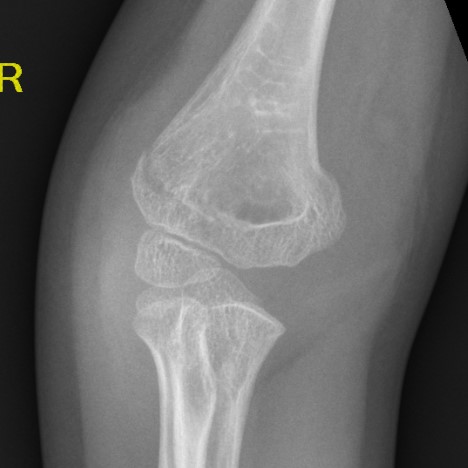

AP X-ray

Baumann's Angle

Technique

- angle between longitudinal axis humerus and capitellar physis

- should equal uninjured side

- 75o normal

Cubitus varus

- varus malposition > 81°

Cubitus valgus

- < 70o